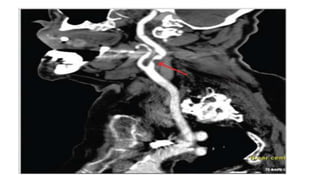

• Urgent imaging using CT/CT angiography can identify patients at high risk

for recurrent stroke.

• CTA is a quick and easy addition to the noncontrast CT that is completed on

most patients and provides much more information than a noncontrast CT

alone, with imaging of the intracranial and extracranial vessels.

• The addition of better imaging techniques, such as multiphase CTA and CT

perfusion, provides the ability to identify more distal occlusions than

previously. Evidence of 50% or greater stenosis or occlusion in a symptom

relevant vessel in the intracranial or extracranial circulation puts a patient

at high risk of a recurrent stroke

• Head CT was normal, but CT angiography showed a high-grade stenosis of the right

internal carotid artery.